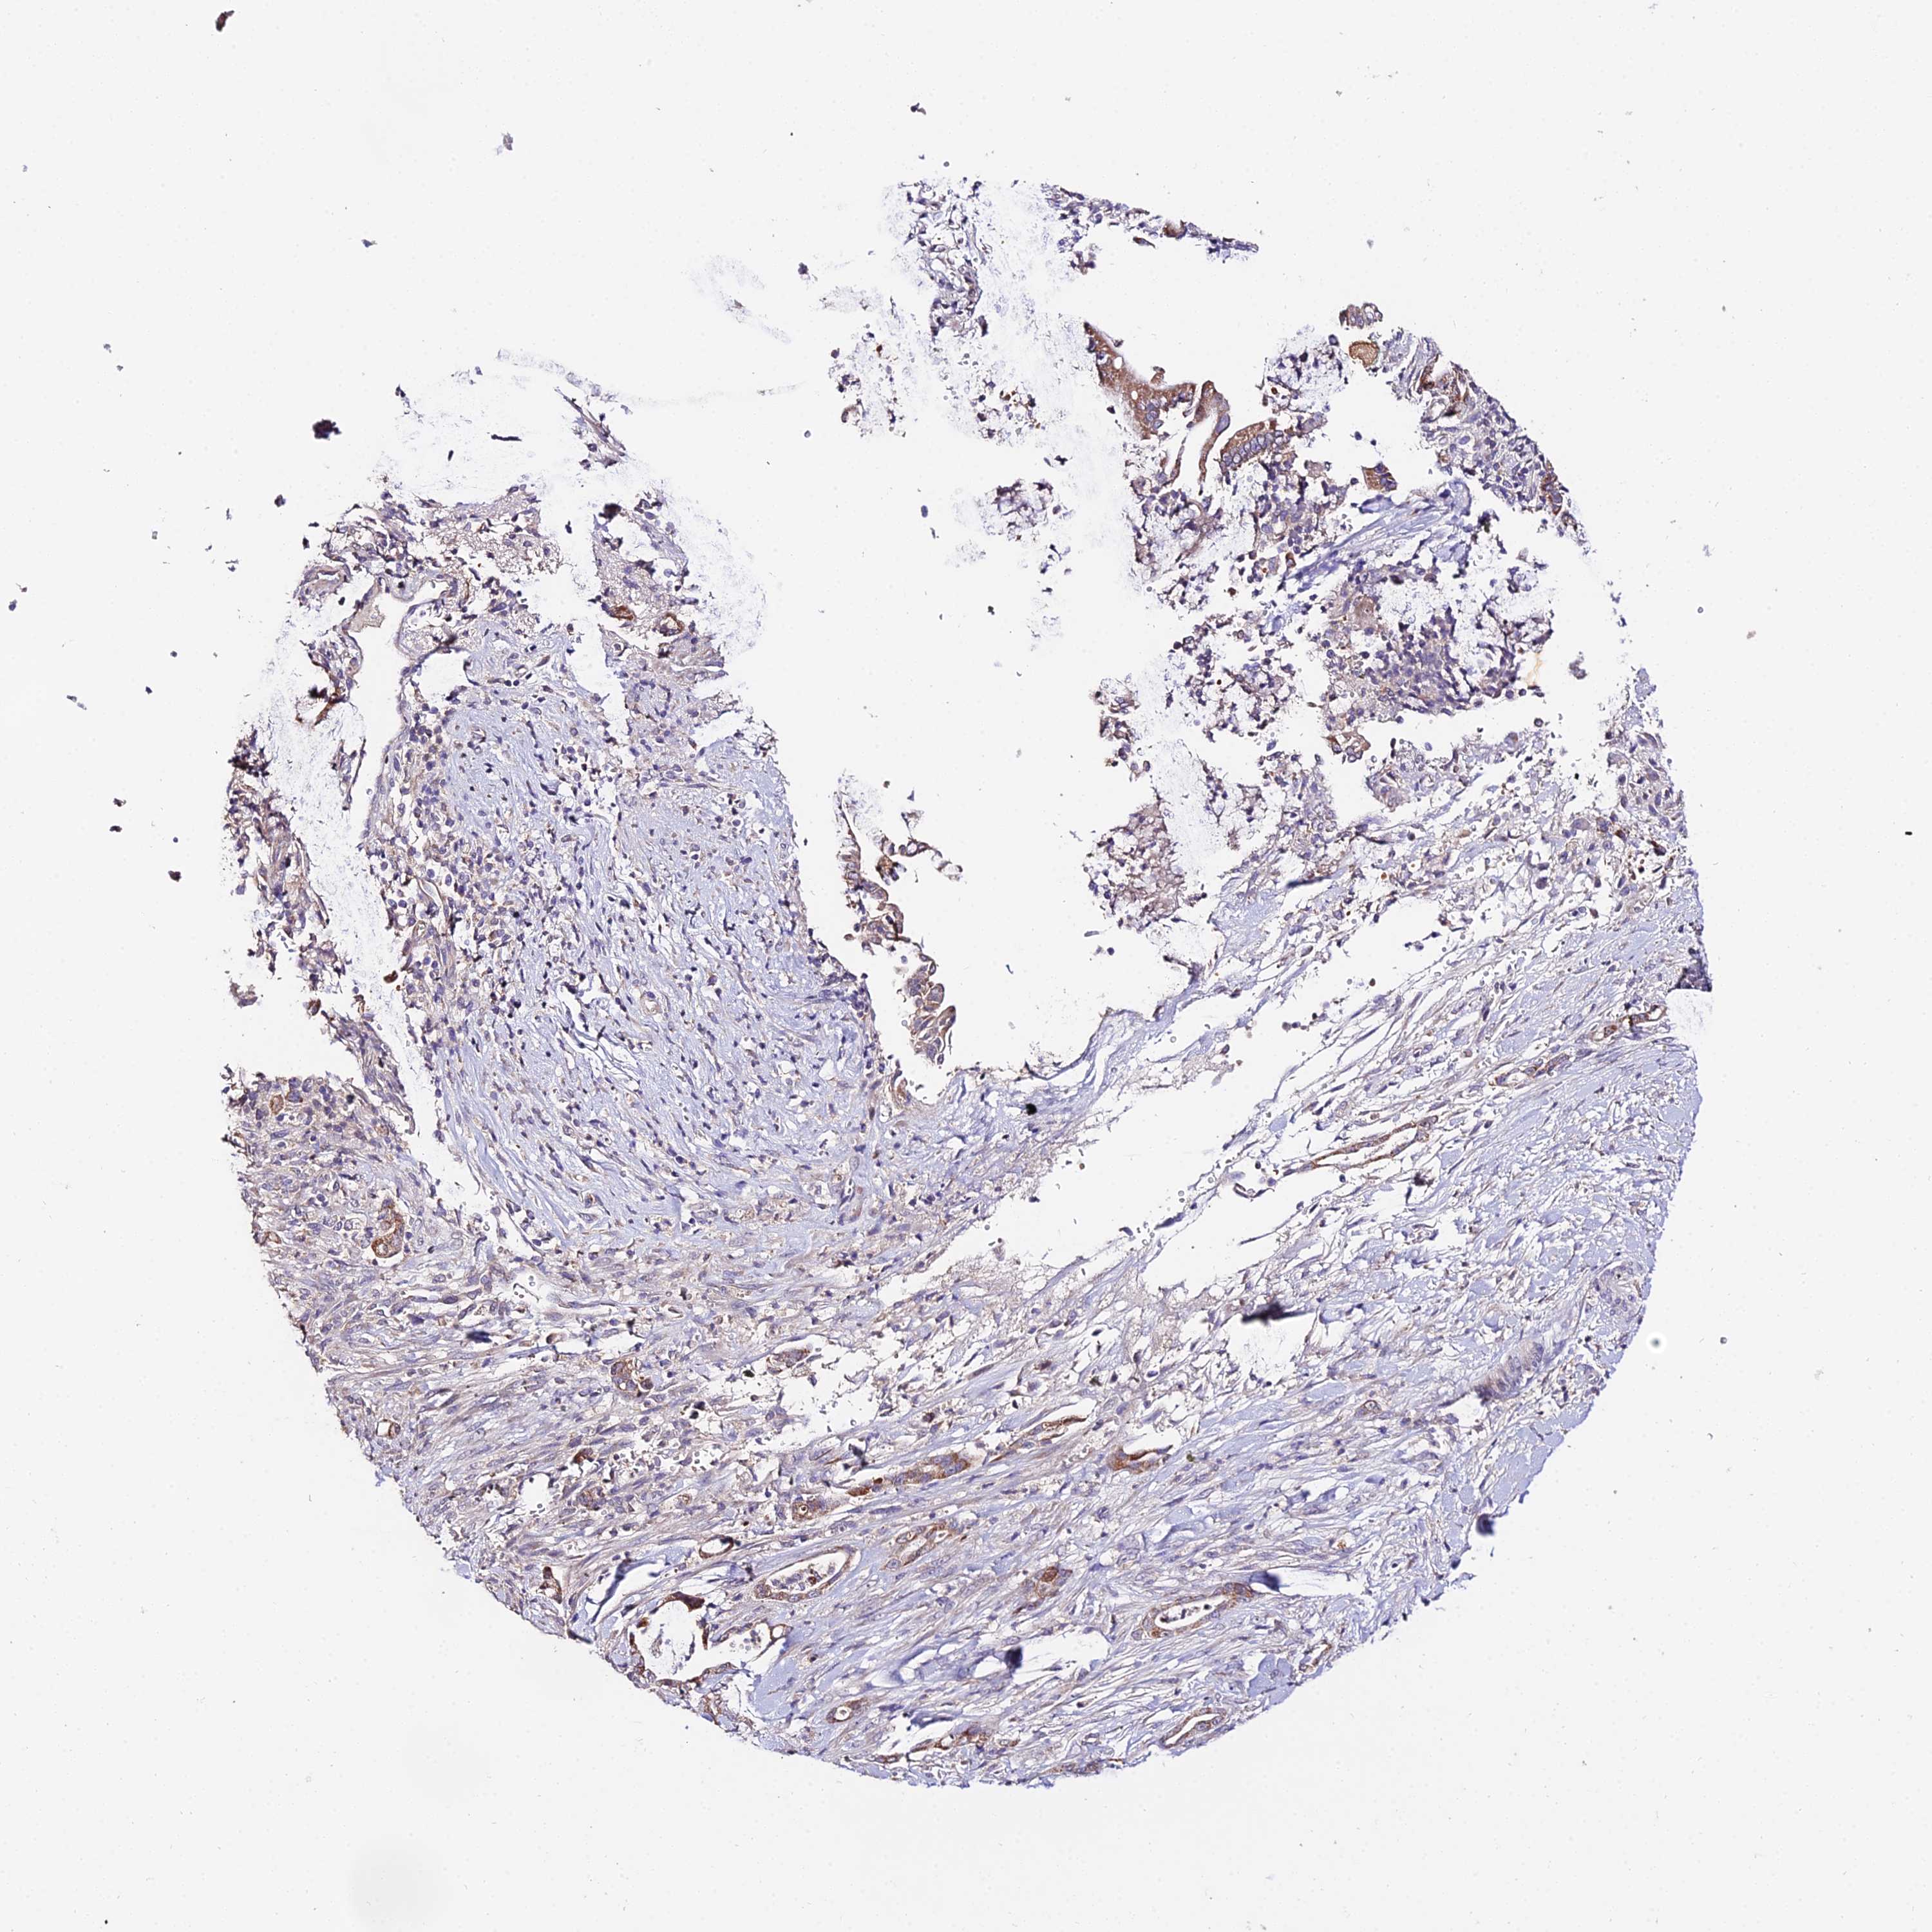

PANCREATIC CANCER - Protein expressioni

A mouse-over function shows sample information and annotation data. Click on an image to view it in a full screen mode. Samples can be filtered based on level of antibody staining by selecting one or several of the following categories: high, medium, low and not detected. The assay and annotation is described here.

Note that samples used for immunohistochemistry by the Human Protein Atlas do not correspond to samples in the TCGA dataset.

Antibody stainingi

Antibody staining in the annotated cell types in the current human tissue is reported as not detected, low, medium, or high, based on conventional immunohistochemistry profiling in selected tissues. This score is based on the combination of the staining intensity and fraction of stained cells.

Each image is clickable and will lead to virtual microscopy that enables deeper exploration of all samples and also displays staining intensity scores, fraction scores and subcellular localization as well as patient and tissue information for each sample.

Antibody HPA042994

Staining

High

Medium

Low

Not detected

Intensity

Strong

Moderate

Weak

Negative

Quantity

>75%

75%-25%

<25%

None

Location

Nuclear

Cytoplasmic/membranous

Cytoplasmic/membranous,nuclear

Adenocarcinoma, NOS